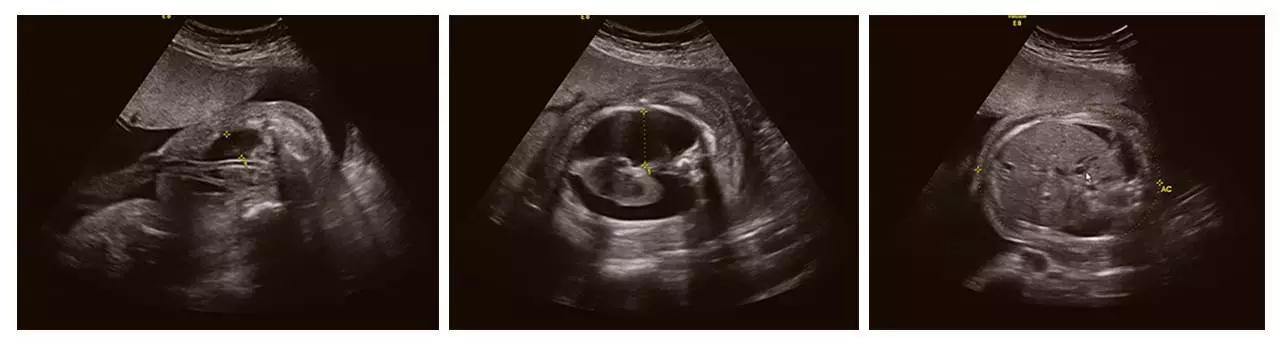

成功筛查胎儿畸形的案例(部分)

(右手多指畸形)

(单侧唇裂)

(双侧唇裂)

(左心发育不良)

(胸腹腔积液、全身水肿)

(颈后水囊瘤)

(胎儿左手未见,考虑截肢畸形)

(胎儿颅内结构异常、眼距窄、鼻结构异常...)

以上案例更多的是警示我们超声影像(四维彩超)检查的重要性。我们希望每个宝宝都能健康成长。